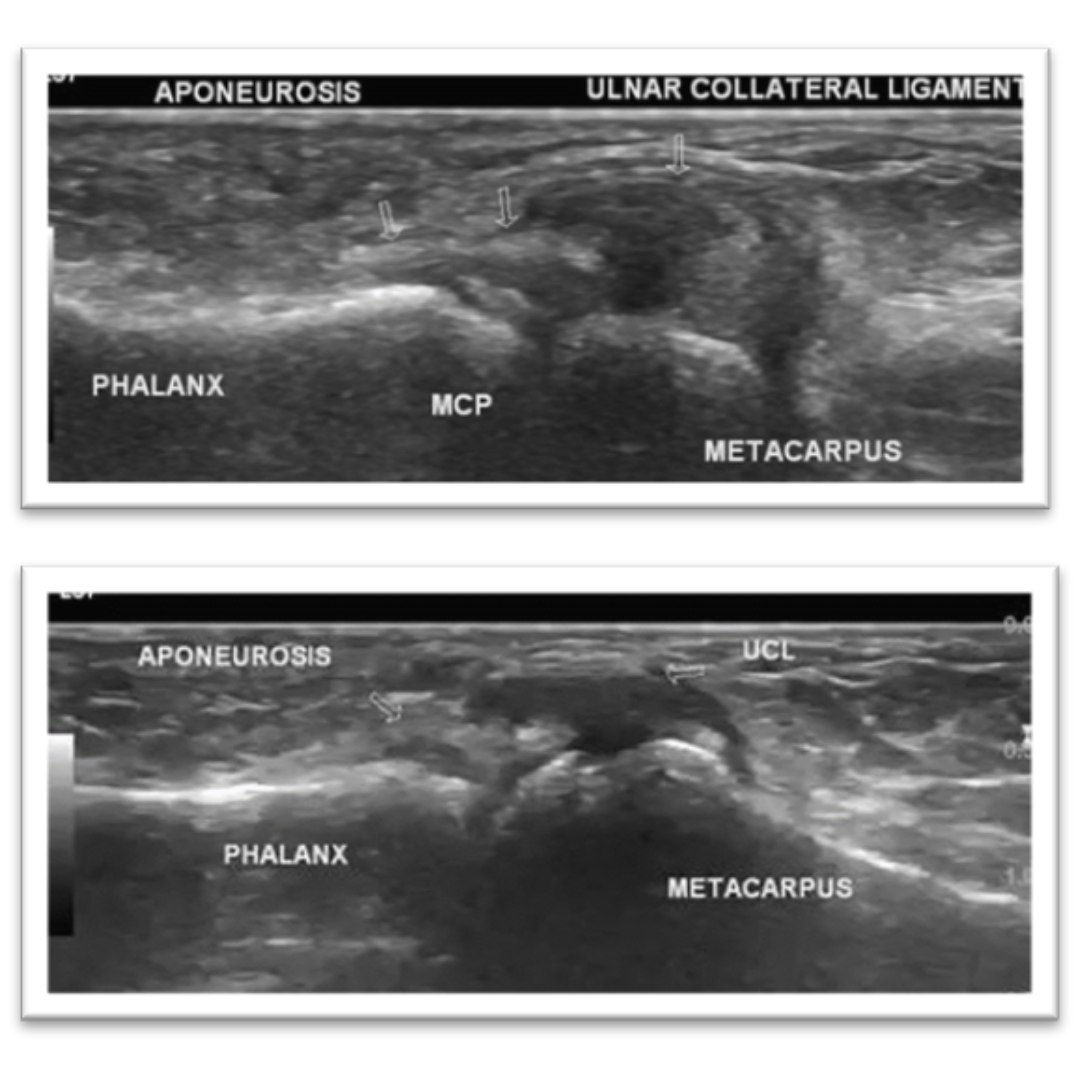

Lesión de Stener

Rotura total del LCC con retracción de cabo proximal que resulta en la interposición de la aponeurosis del músculo aductor corto del pulgar entre el LCC y la art MTC-F. Ecográficamente se visualiza:

· Imagen pseudonodular correspondiente a cabo del ligamento retraído.

· Visualización de la aponeurosis del aductor corto entre la art MTC-F y el cabo del LCC.

· Maniobra dinámica de flexo-extensión comprueba interposición de aponeurosis.